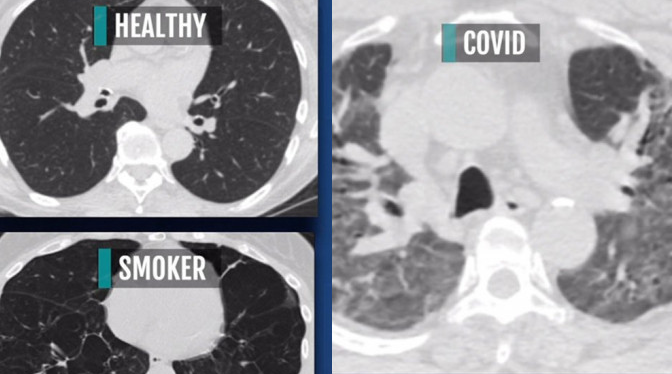

新冠肺炎患者的肺部(右圖)一片花白。(網絡截圖)

米蕭德對比3張斷層掃瞄影像,分別為一般人、吸煙者,以及新冠患者的肺部狀態。她指出,一般人的肺部X光片應該是大部分呈現黑色,代表充滿空氣;而吸煙者的肺部則有部分白點;至於新冠肺炎患者的肺部,則幾乎是一片白色的嚴重「傷疤」,並指這些白色「傷疤」就像是混凝土,會影響氧氣進入肺部。

她形容新冠肺炎患者就像是得了末期肺病,嚴重程度就像是吸煙數十年的人,唯一的區別是在時間上,新冠肺炎只是幾天的事。